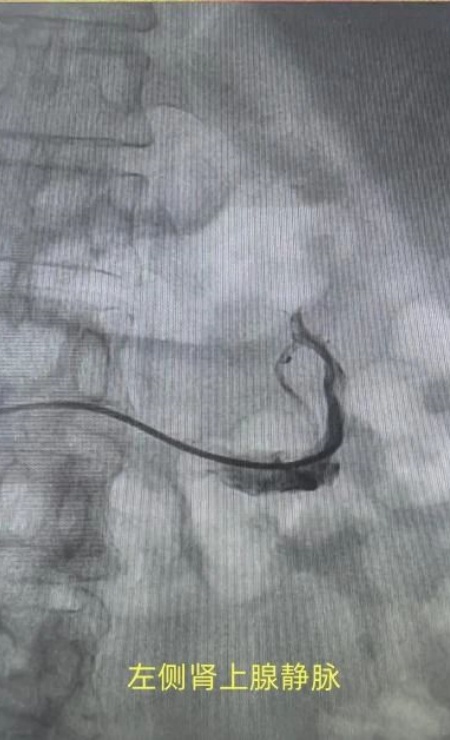

患者张xx,深受高血压困扰8年,血压却始终难以得到有效控制,本次入院前2天在家自测血压210/110mmHg,佟勤红主任带领团队对患者进行了全面、细致的评估后,高度怀疑患者为原发性醛固酮增多症。而双肾静脉采血,作为诊断该病手术治疗的“金标准”检查手段,能够通过精准检测双侧肾静脉血中醛固酮及肾素水平,明确肾上腺病变的侧别,从而为后续的个性化治疗方案制定提供关键依据。

手术当日,在佟勤红主任的精准指导下,心内一科手术团队凭借娴熟的操作技巧和丰富的临床经验,有条不紊地开展手术。从穿刺血管、置入导管到精准采集双侧肾静脉血,每一个步骤都严谨规范、环环相扣。整个手术过程顺利,患者生命体征平稳。目前,患者的血样已完成送检,确诊为单侧肾上腺腺瘤所致的原发性醛固酮增多症,患者可通过手术切除腺瘤,有望实现高血压的治愈。